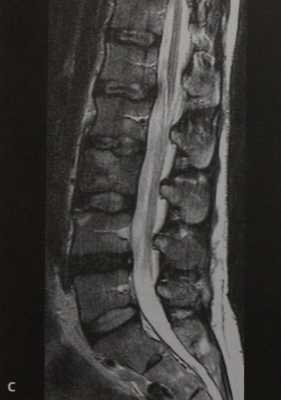

а-с Женщина 38 лет с анапластической неходжкинской лимфомой и вторичным поражением 1.3. (а) 16-срезовая КТ, сагиттальная реконструкция. Преимущественно склеротическая плотность поражения с компрессией позвонка, поражающей верхнюю замыкательную пластинку;

(b) Т1-взвешенная последовательность. Диффузное снижение МР-сигнала от костного мозга пораженного позвонка по сравнению с МР-сигналом от костного мозга здоровых позвонков. Инфильтрация тела позвонка выражена менее интенсивно в сравнении со здоровым костным мозгом,

с Т2-взвешенная последовательность. Гипоинтенсивный сигнал 1.3 вследствие формирования новой кости.